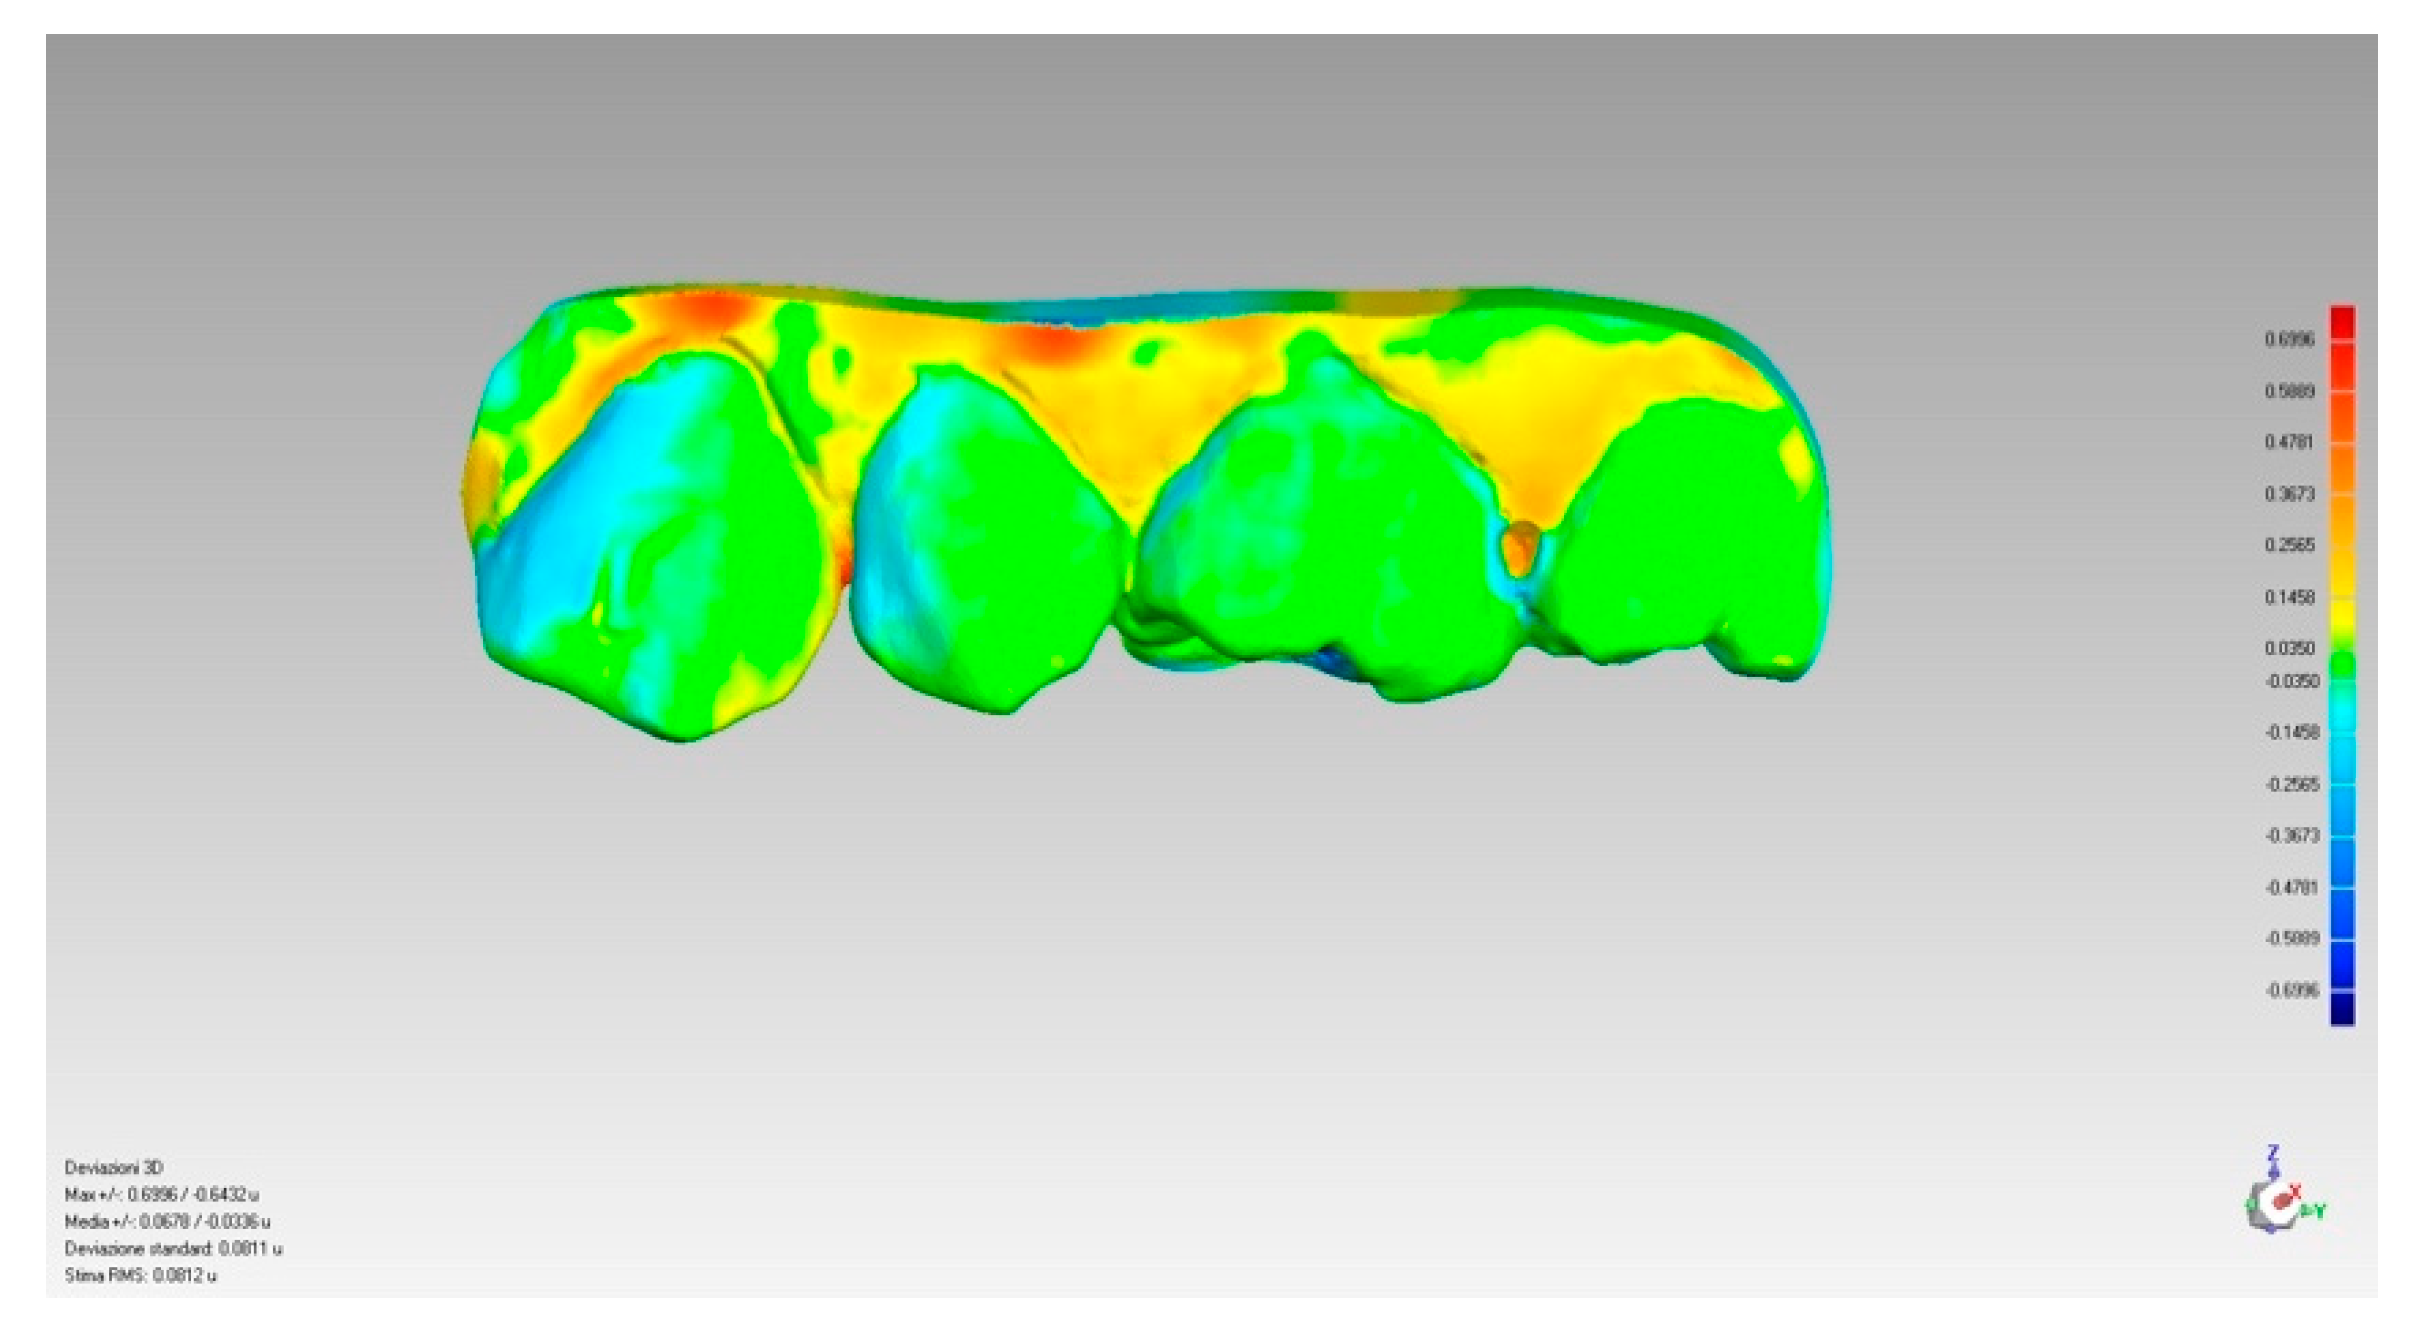

2.5. Treatment of the Collected Data

3. Results